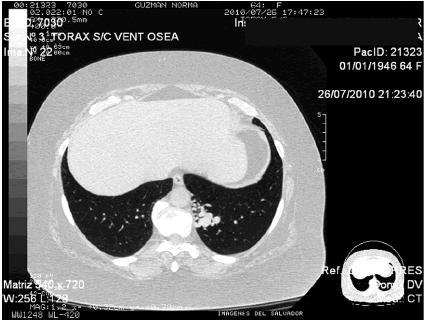

La paciente concurre a la consulta con las siguientes imágenes TAC de tórax (Imagen N° 2 y 3) RMN de tórax (Imagen N° 4).

Dr. Marcos Langer: Vista ahora la tomografÃa de tórax, se puede interpretar que las imágenes nodulares retrocardÃacas que se observan en la radiografÃa de tórax podrÃan corresponder a lesiones o malformaciones arterio-venosas pulmonares.

Dr. Juan P. Casas: Se podrÃa pensar que son lesiones vasculares de acuerdo a la morfologÃa de los hallazgos. Ante imágenes redondeadas periféricas, en el contexto de esta paciente con historia de hipoxemia y asociado a los hallazgos del examen fÃsico que son cianosis e hipocratismo digital podrÃan corresponder a malformaciones arteriovenosas (MAV), por lo que sugerirÃa realizar una angiotomografÃa. Las imágenes nodulares que se visualizan también pueden corresponder a otros diagnósticos diferentes.

Dr. Juan P. Casas: La TAC de tórax con contraste puede diferenciar si la imagen es vascular o no, ya que nos brindarÃa información no sólo de la existencia de las fÃstulas AV, sino también del número, origen y tamaño de los vasos aferentes y eferentes. También se puede realizar un ecocardiograma con contraste, con este estudio, inyectando contraste en una vena periférica se puede diagnosticar un shunt intracardÃaco en el caso de que luego de un ciclo cardÃaco, es decir, a los 3 segundos posteriores a haber visto el contraste en la aurÃcula derecha, se detecta el mismo en las cavidades izquierdas. En las MAV el tiempo que transcurre en pasar el medio de contras de las cavidades derechas a las izquierdas es de 5 a 9 segundos, es decir 2 a 5 ciclos cardÃacos. Nosotros vemos una lesión bastante localizada en la base izquierda que podrÃa corresponder a un secuestro.

Dra. Ana López: Comparto tu opinión, en un primer momento pensé en secuestro por la localización basal pulmonar izquierda, que es la descripción clásica. Sin embargo, este se pone en evidencia generalmente con infecciones porque no tiene una ventilación adecuada, otro dato en contra de secuestro es que este tiene una o varias arterias aferentes que dependen de la circulación sistémica, pero no tiene la repercusión clÃnica con policitemia e hipocratismo digital, ni tampoco la severa hipoxemia que presenta nuestra paciente y que es secundaria al shunt intrapulmonar de derecha a izquierda.